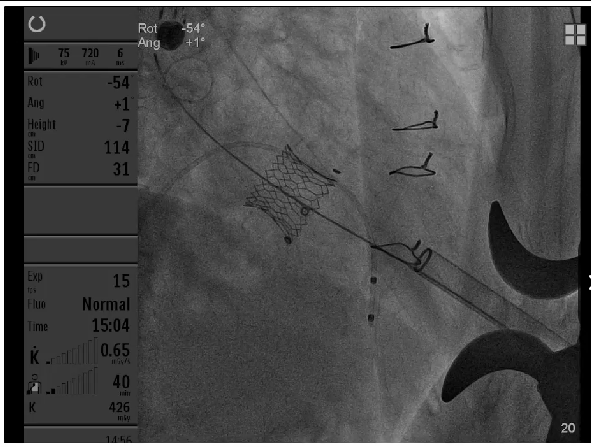

25#Renatus瓣膜释放

Atlas Gold球囊高压力后扩,扩断25#Mosaic瓣膜

瓣膜释放后状态

第一次高压球扩后形态

第二次高压球扩后形态